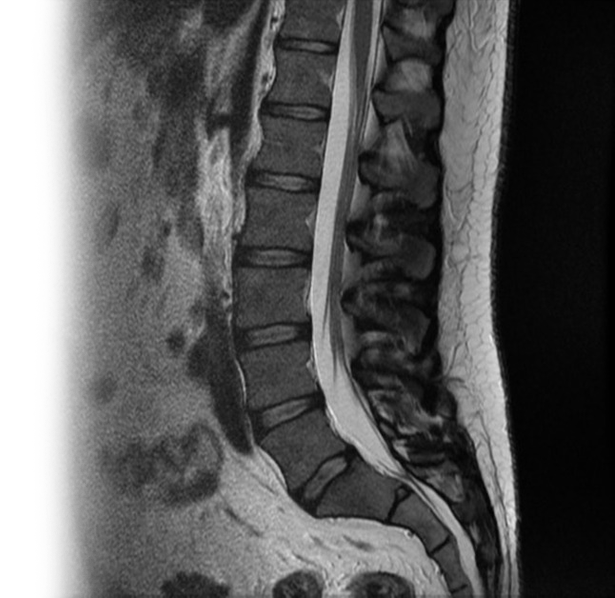

Магнитно-резонансная томография одного отдела позвоночника с контрастированием – важный метод исследования с введением контрастного вещества, который позволяет визуализировать позвонки и спинной мозг, окружающие мягкие ткани.

Перед укладкой в томограф необходимо снять все металлические предметы. Перед процедурой устанавливается внутривенный катетер для введения контрастного препарата непосредственно во время исследования. После этого пациент ложится на стол сканера, который постепенно перемещается в аппарат. Во время сканирования следует лежать неподвижно, чтобы получаемые изображения были четкими и неискаженными.